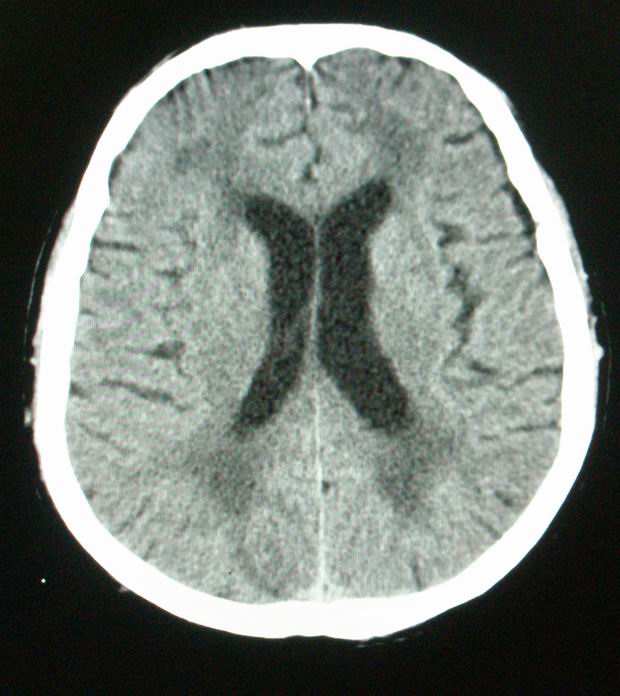

以下是引用随光逐影在2008-4-5 7:46:00的发言:[br]1)考虑为:多发性脑转移瘤。建议:行进一步检查。2)多发性腔隙性脑梗塞。3)脑白质病。4)脑萎缩。

以下是引用zjzjr在2008-4-5 9:00:00的发言:[br]1.双侧颞叶占位性病变,考虑为转移瘤可能性大。[br]2.左侧基底节区陈旧性腔隙性脑梗塞。[br]3.脑白质病。建议mri进一步检查。

以下是引用xuhuihong在2008-4-5 0:59:00的发言:[br]1.双侧颞叶占位性病变,考虑为转移瘤可能性大。[br]2.左侧基底节区陈旧性腔隙性脑梗塞。[br]3.脑白质病。建议mri进一步检查。

以下是引用形影不离在2008-4-4 23:29:00的发言:[br]1.双侧颞叶占位性病变,考虑为转移瘤可能性大。[br]2.左侧基底节区陈旧性腔隙性脑梗塞。[br]3.脑白质病。